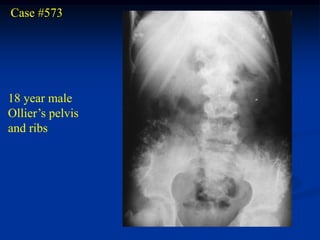

Case #573

18 year male

Ollier’s pelvis

and ribs